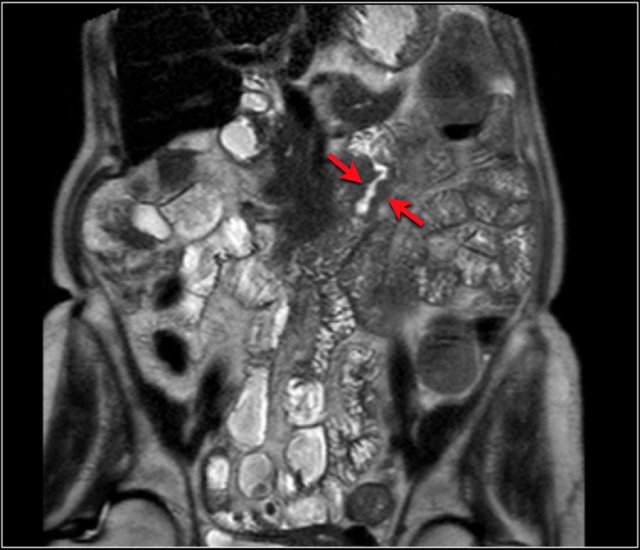

Top images show a circular mass in the proximal jejunum with FDG uptake (yellow arrows).

Lower MR-images show the same jejunal mass with shouldered borders and mesenteric lymphadenopathy (red arrows), consistent with adenocarcinoma.